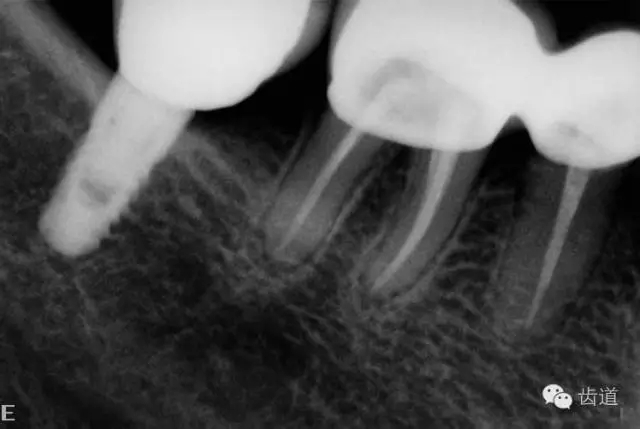

2、45,46術(shù)前片顯示根管上段充填物,根管影像不清晰,少許根尖暗影

6、45,46,47牙片